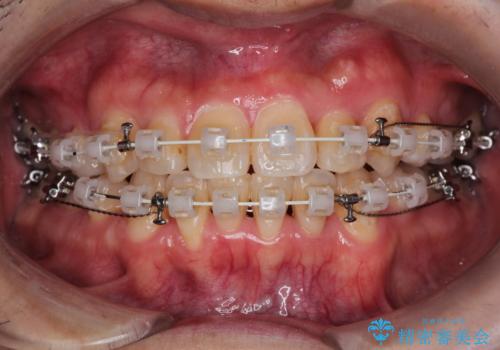

- 矯正装置

- 審美装置

難しいケースでしたが、矯正用アンカースクリューを用いながら、臼歯関係もきれいに仕上げることができました。